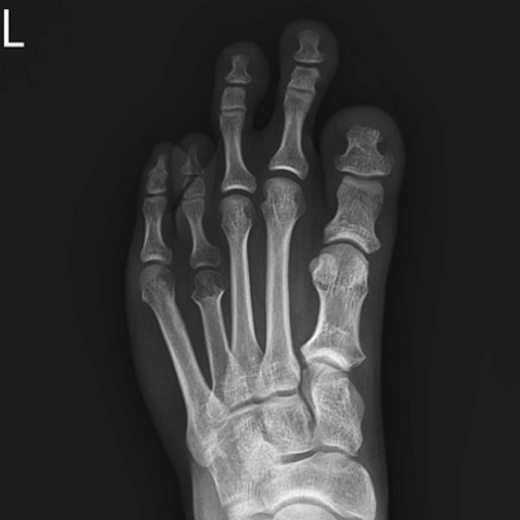

정상 발

단지증

단지증 수술 전/후 예시

단지증 수술 전

2020.01.09